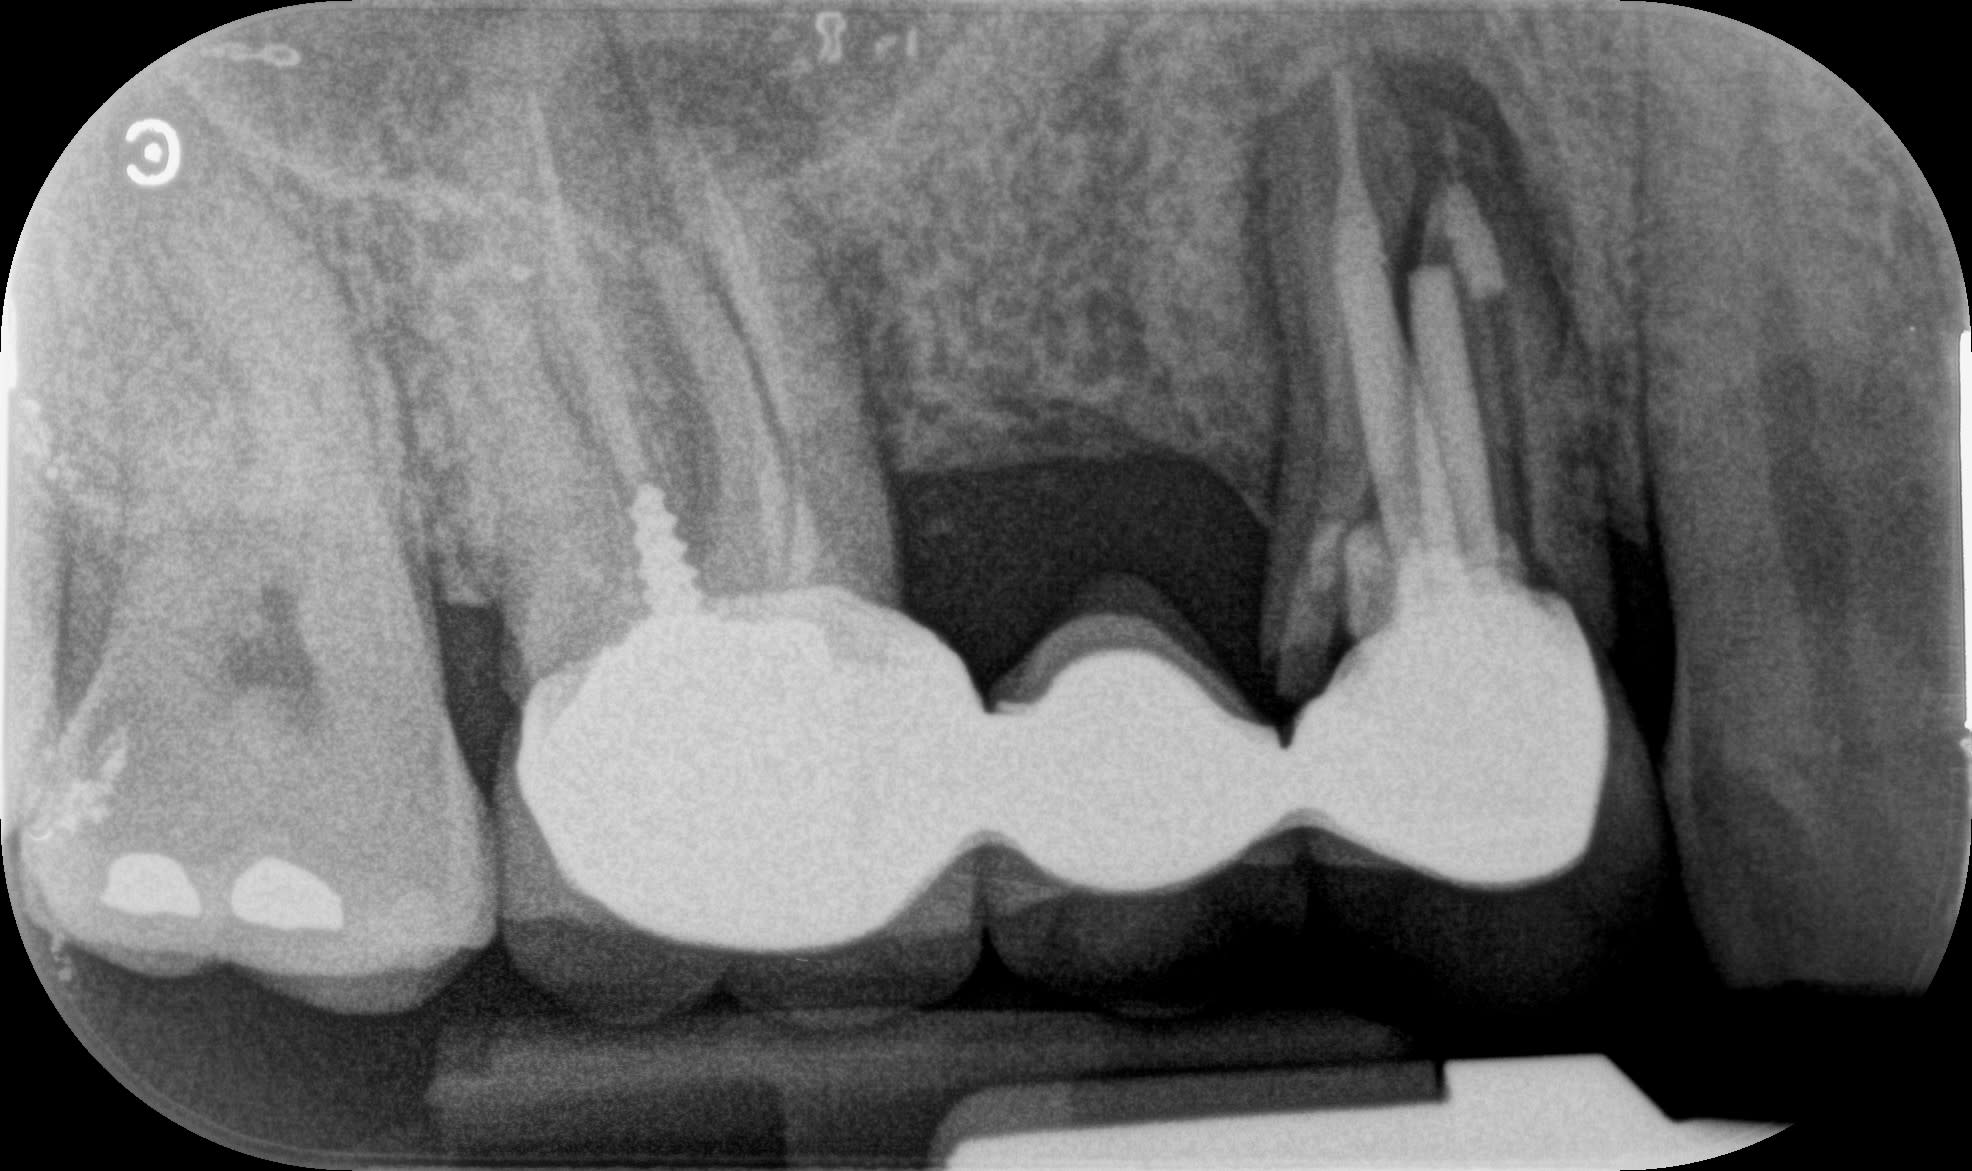

Un petit cas fini il y a deux ans, de l'omni pratique de bout en bout.

Est-ce bien raisonnable? ou trop de facteurs de risque.

Je me pose toujours la question.

Je pense que chez un spécialiste la molaire serait aujourd’hui un implant et pas une molaire avec une amputation radiculaire.

Bravo, très bien manager.

Et pour ma part je n'aurais pas solidarisé.

Avec des implants courts au maxillaire, la solidarisation ne me choque pas, au contraire.